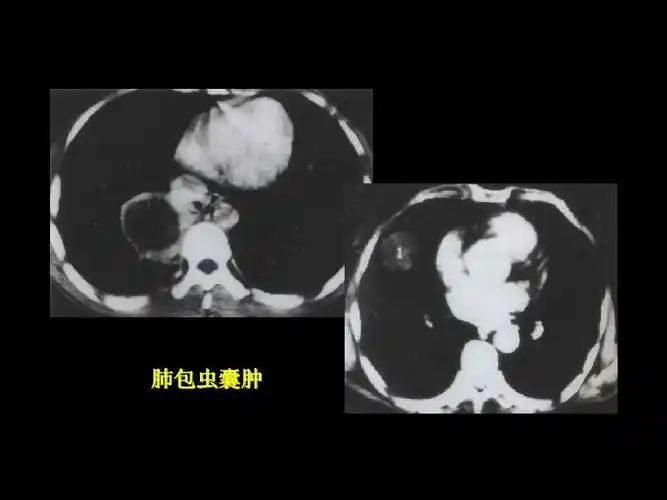

肺包虫囊肿